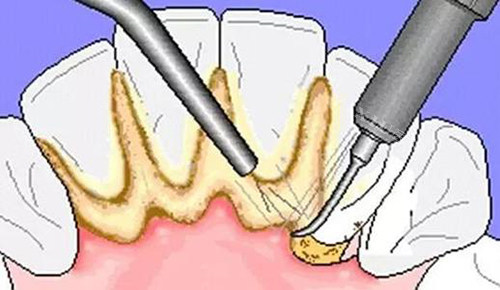

一、洗牙服务

洗牙是预防和治疗牙周疾病的基础项目,郑州颐和医院口腔科的洗牙价格为120元起。医院提供多种洗牙套餐,包括普通超声波洗牙和喷砂洁牙等,能够有效去除牙结石和牙渍,帮助患者保持口腔健康。